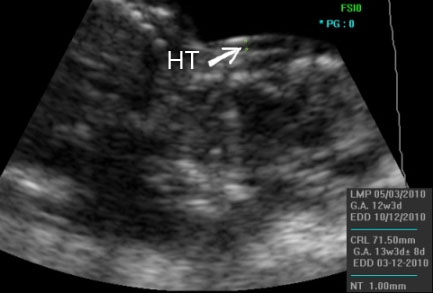

Нухална транслуценца (НТ) или дебелина на кожниот набор на задната страна на вратот на бебето е параметар кој се смета за значаен показател на присуството или отсуството на Down-овиот синдром. Вообичаено дебелината на наборот изнесува околу 1 mm. Поголема дебелина на наборот може да означува и поголема веројатност за присуство на Down-ов синдром, па во тој случај треба да се направат некои дополнителни испитувања. Како маркер за правилниот развој на бебето се испитува и присуството на носната коска на лицето.

Покрај овие параметри, на овој преглед се испитува и мотилитетот (подвижноста) на бебето, се испитува растот, се земаат вообичаените мерки и се проверува дали големината на бебето соодветствува со неговата гестациска старост. Должината на бебето (CRL) изнесува околу 50 – 60 mm.

Во продолжение Ви презентираме неколку УЗ слики од прегледот во 12. недела.